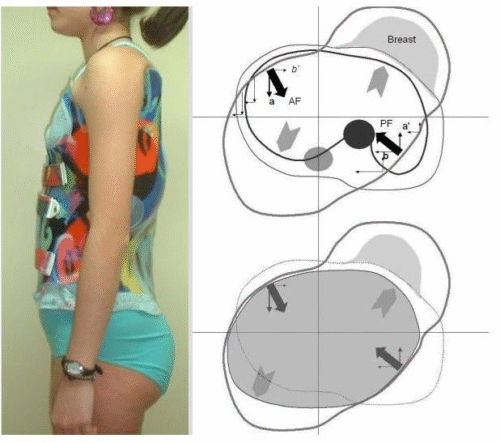

التطور الكبير في تصميم الأحزمة الطبية جعل علاج اعوجاج العمود الفقري عند المراهقين أكثر نجاحًا وأقل إزعاجًا. باستخدام تقنيات التصوير الثلاثي الأبعاد والمحاكاة الرقمية، أصبح الحزام أكثر خفة وراحة، ويعطي نتائج أفضل في تصحيح الانحناء والتواء العمود الفقري.

الرسالة للأهل: إذا كان طفلك بحاجة إلى حزام طبي، اسأل الطبيب دائمًا عن التصميم الحديث المصنوع بتقنية ثلاثية الأبعاد، لأنه قد يكون الفرق بين علاج ناجح وفعّال، وبين نتائج محدودة.

امنح طفلك فرصة أفضل لمستقبل صحي مع حزام PioBrace المتطور من مركز الرواد. يتميز هذا الحزام بتقنيات تقويم متقدمة تضمن نسبة تصحيح عالية لاعوجاج العمود الفقري، مع اعتماد فريق طبي متخصص يراقب التقدم بشكل مستمر لضمان عدم تفاقم الانحناء مستقبلاً. اختروا مركز الرواد، حيث تلتقي الخبرة الطبية بأحدث الابتكارات، لنوفر لطفلكم علاجًا مخصصًا وآمنًا يعيد التوازن لجسمه بثقة واحترافية. صحتهم أمانة ونحن هنا لنحافظ عليها.

لماذا يجب عليكم اختيار حزام PioBrace؟

- راحة استثنائية: يتميز حزام PioBrace بتصميمه الذي يوفر أقصى درجات الراحة للأطفال طوال فترة العلاج.

- فعالية مثبتة علميًا: يساعد الحزام في إيقاف تقدم الاعوجاج وتقليل الحاجة إلى التدخل الجراحي.

- سهولة الاستخدام: يمكن ارتداؤه لفترات طويلة دون التسبب في أي إزعاج للأطفال.

- موثوقية وجودة عالية: يُصنع بأحدث التقنيات لضمان أقصى درجات الراحة والكفاءة.